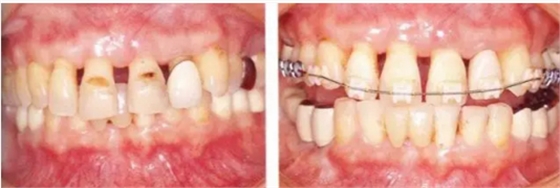

病例7

在正畸治療結(jié)束后仍然存在open contact的病例

▲圖15-1,2

在正畸??漆t(yī)生處接受了正畸治療,雖然上頜正畸治療已經(jīng)完成,但由于磨牙區(qū)的邊緣嵴不整齊而導(dǎo)致牙體之間存在空隙。要想在這個狀態(tài)下護(hù)理牙周組織以及咬合狀況是非常困難的。由此可見,在治療時,正畸??漆t(yī)生與全科口腔醫(yī)生保持目標(biāo)一致是非常重要的。